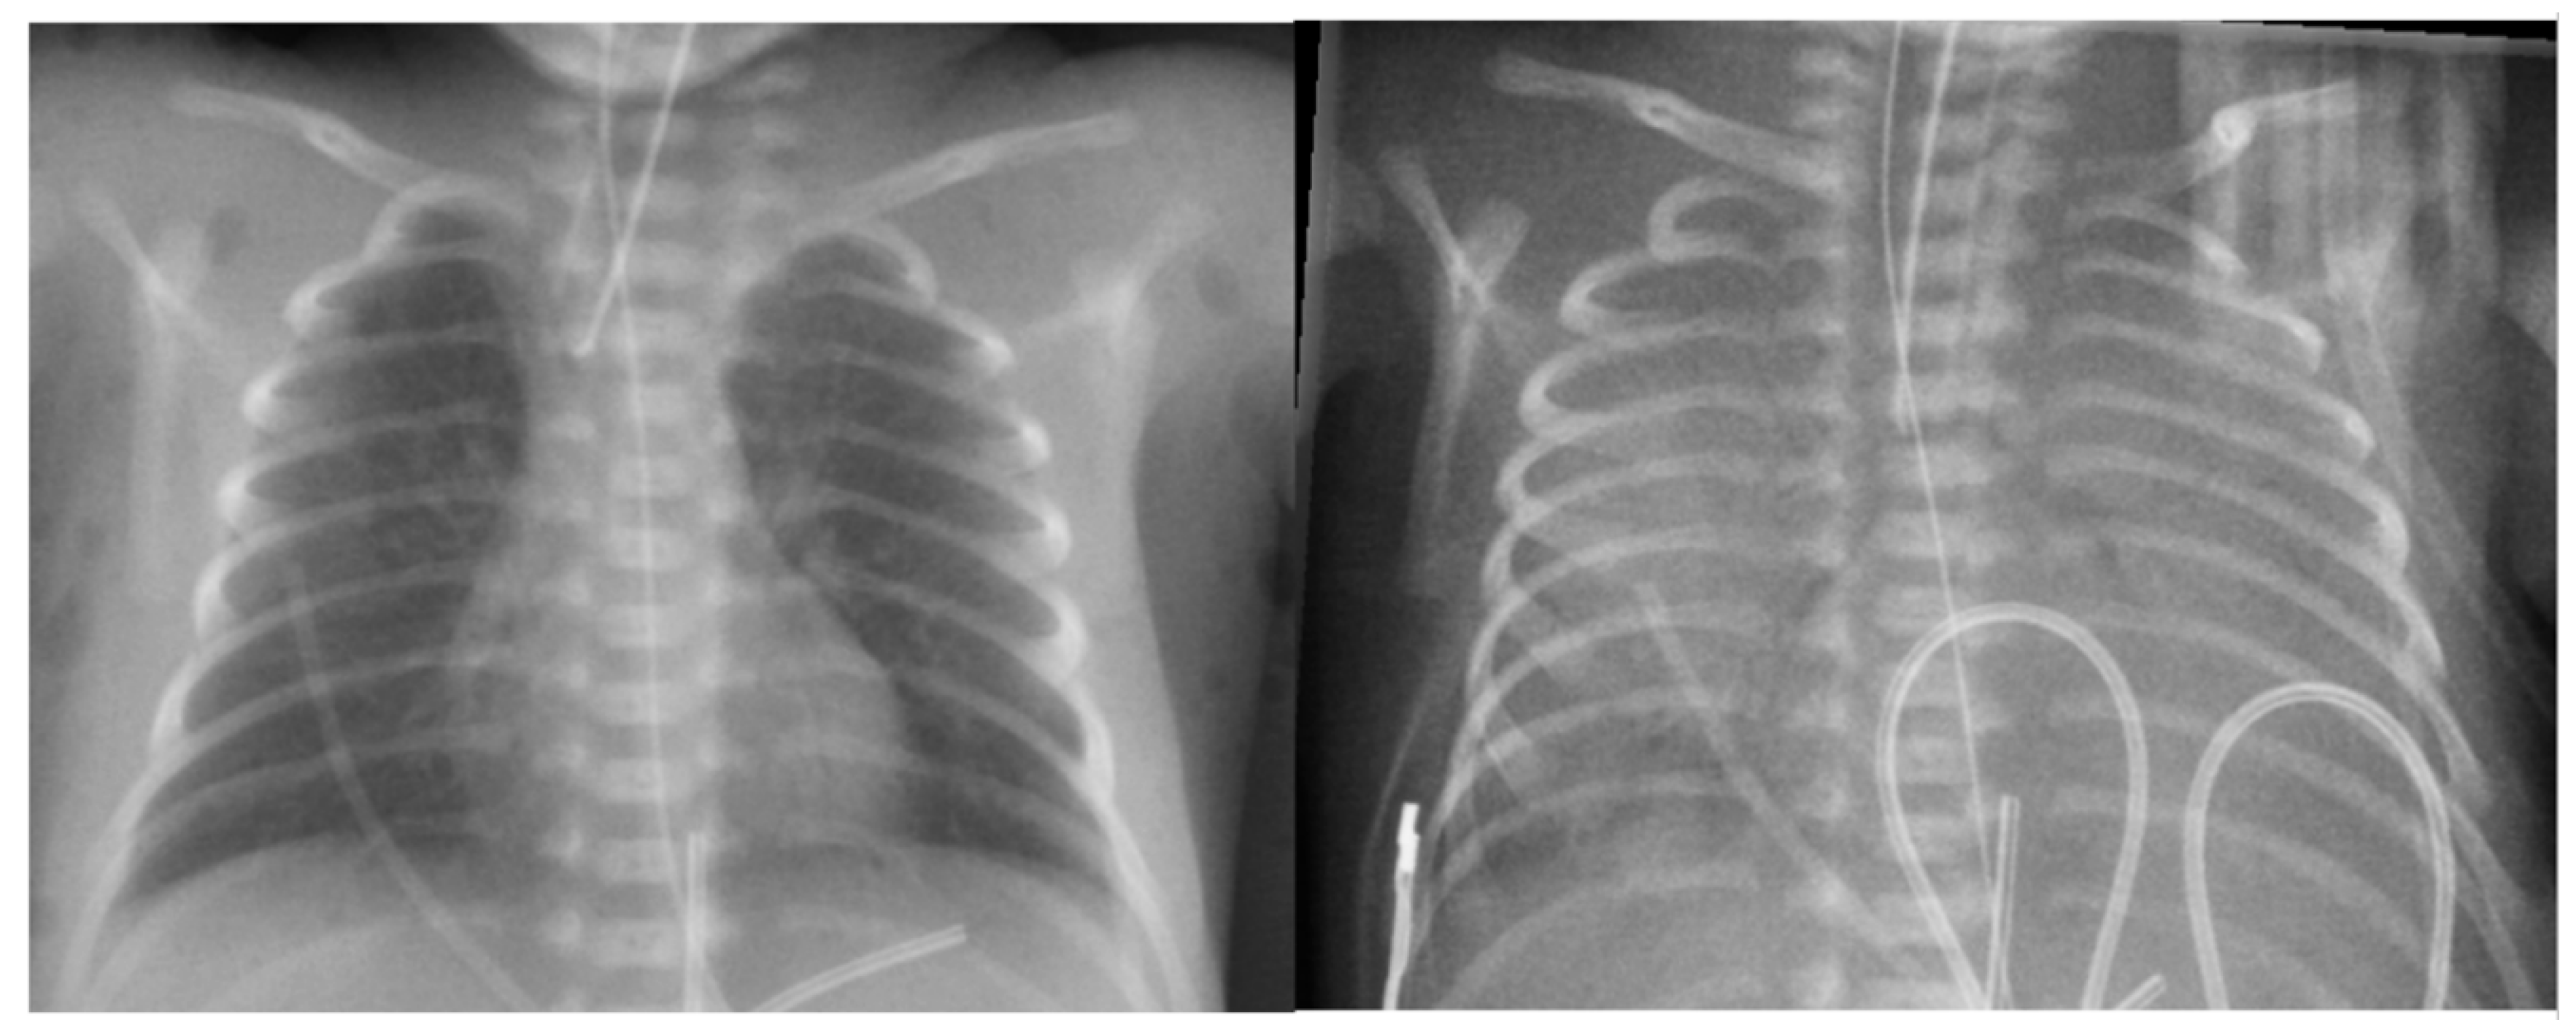

6.3. Radiological Diagnosis